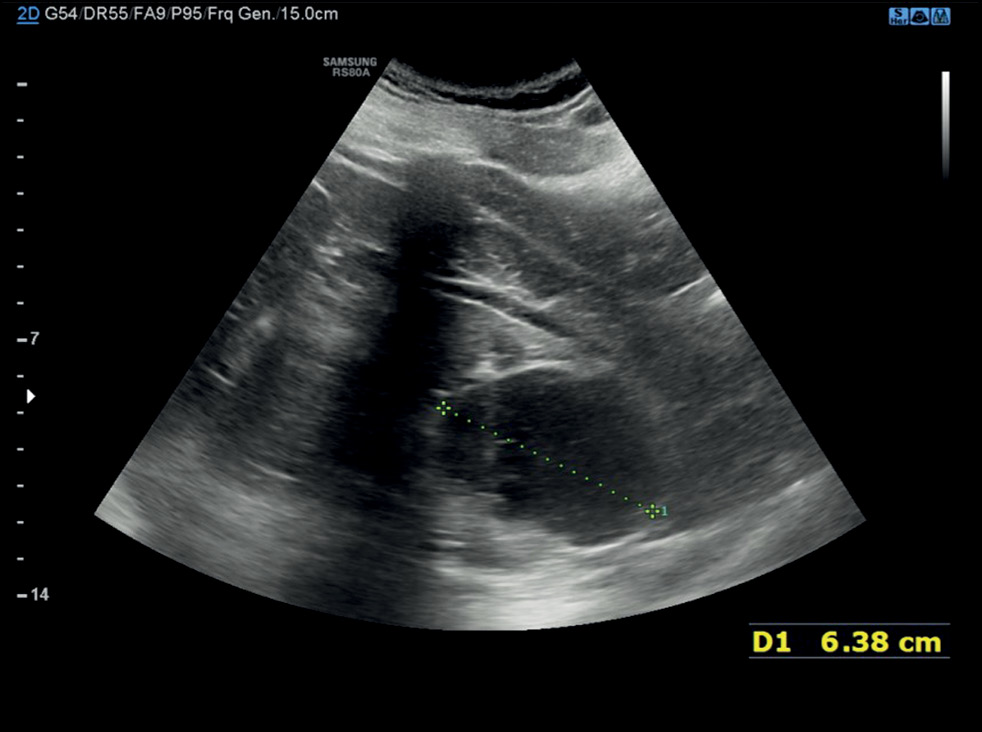

Calyceal diverticula, also known as pyelogenic cysts, are a relatively uncommon condition, which is usually asymptomatic and incidentally diagnosed during routine imaging. In some cases, they may lead to concerning symptoms such as hematuria and flank pain, mimicking a renal tumor. In this case report, the patient suffered from hematuria that was initially suspected as a renal malignancy but was ultimately attributed to a calyceal diverticulum. The presented case allows evaluating one of the rarest and underestimated causes of hematuria and describes the main imaging features of calyceal diverticula. In particular, ultrasonography, computed tomography urography, dual-energy computed tomography, and magnetic resonance urography were performed. Subsequently, this case report also serves an educational purpose.